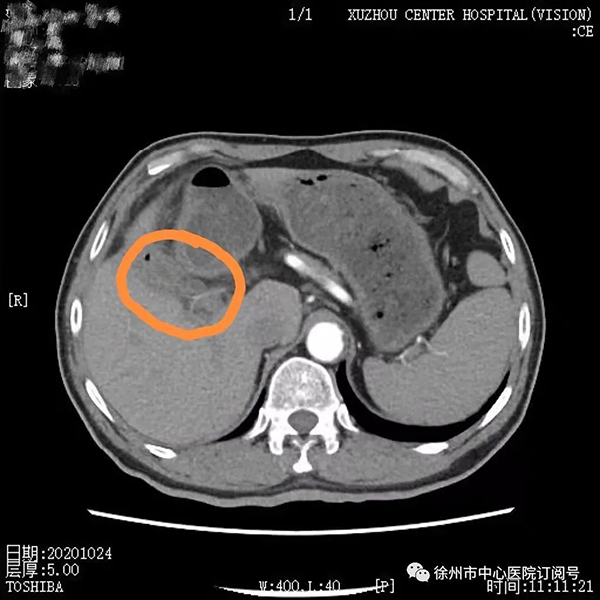

2020年8月,董先生行第一次靶免治療,無特殊不良反應(yīng),后間隔21天行一次治療至第4療程;2020年10月腹部CT檢查見腫瘤較前縮小,病情持續(xù)好轉(zhuǎn);2021年4月進(jìn)行第9療程再次復(fù)查腹部CT顯示,此時(shí)腫瘤較第一次治療時(shí)已明顯縮小。

2020年10月第4療程腹部增強(qiáng)CT:膽囊癌復(fù)查,鄰近肝臟斑片狀低密度較2020年8月明顯縮小、好轉(zhuǎn)。